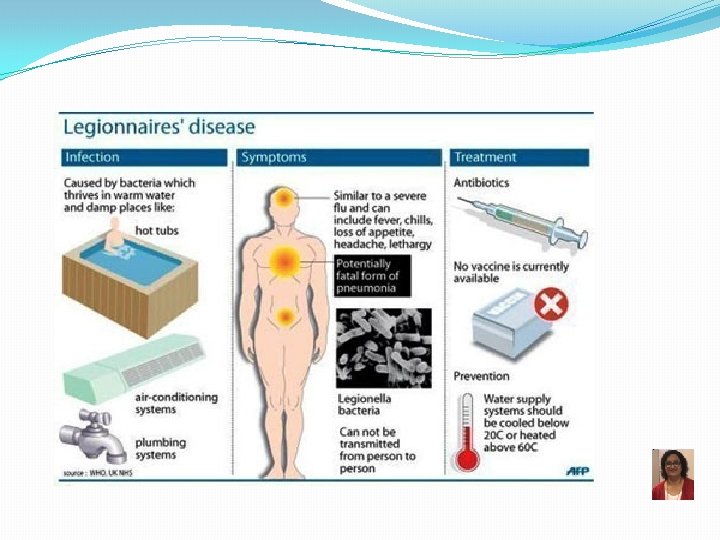

Legionnaire’s Disease Legionella pneumophila Scientists named the bacterium after an outbreak in Philadelphia in 1976. During that outbreak, many people who went to an American Legion convention got sick with pneumonia (lung infection). 89

Epidemiology and Trends Outbreaks are commonly associated with buildings or structures that have complex water systems, like hotels and resorts, long-term care facilities, hospitals, and cruise ships. About one in 10 people who gets sick from Legionnaires’ disease will die Can be transmitted in the hospital set up Keeping Legionella out of water systems in buildings is key to preventing infection. 90

Epidemiology and Transmission No human transmission seen 92

Legionella pneumophila �Weakly staining GNR, better stained with silver stain � Fastidious � Aerobic, motile � 12 serogroups, serogroup 1 most common �Fresh water-loving organism �Facultative intracellular pathogen � Multiples in macrophages Legionnaires’ Disease and Pontiac Fever �Low virulence �Risk groups: older smokers with high alcohol intake, immunocompromised 95

Legionnaires’ Disease Pathogenesis 1) Adheres to respiratory epithelium 2) Attaches to alveolar macrophages coiling phagocytosis 3) Prevents phagosomelysosome fusion 4) Replication inside the macrophage 5) Lysis of phagocytes q Hydrolytic enzymes Lung damage and inflammatory response Reproduced from: Swanson MS, Hammer BK, 2000. Legionella pneumophila pathogesesis: a fateful journey from amoebae to macrophages. Annu. Rev. Microbiol. 54: 567 -613. Legionella is a facultative intracellular pathogen Major role in immunity—cell mediated; Minor role: Humoral immunity 96

Legionnaires’ Disease – Diagnosis �Microscopy �Poorly staining GNR �Direct fluorescent antibody (DFA) �Silver stain �Culture �Fastidious Fluoresceinlabeled antibody attached to Legionella bacilli BCYE � Requires cysteine and iron � Buffered charcoal yeast extract (BCYE) (Legionella rides its Bi. CYcl. E) �Urinary antigen test �Serogroup 1 only Legionella urinary antigen card 97

Legionnaires’ Disease Treatment and Prevention • Treatment ▫ Azithromycin ▫ Levofloxacin • Prevention ▫ Disinfection of water systems 98